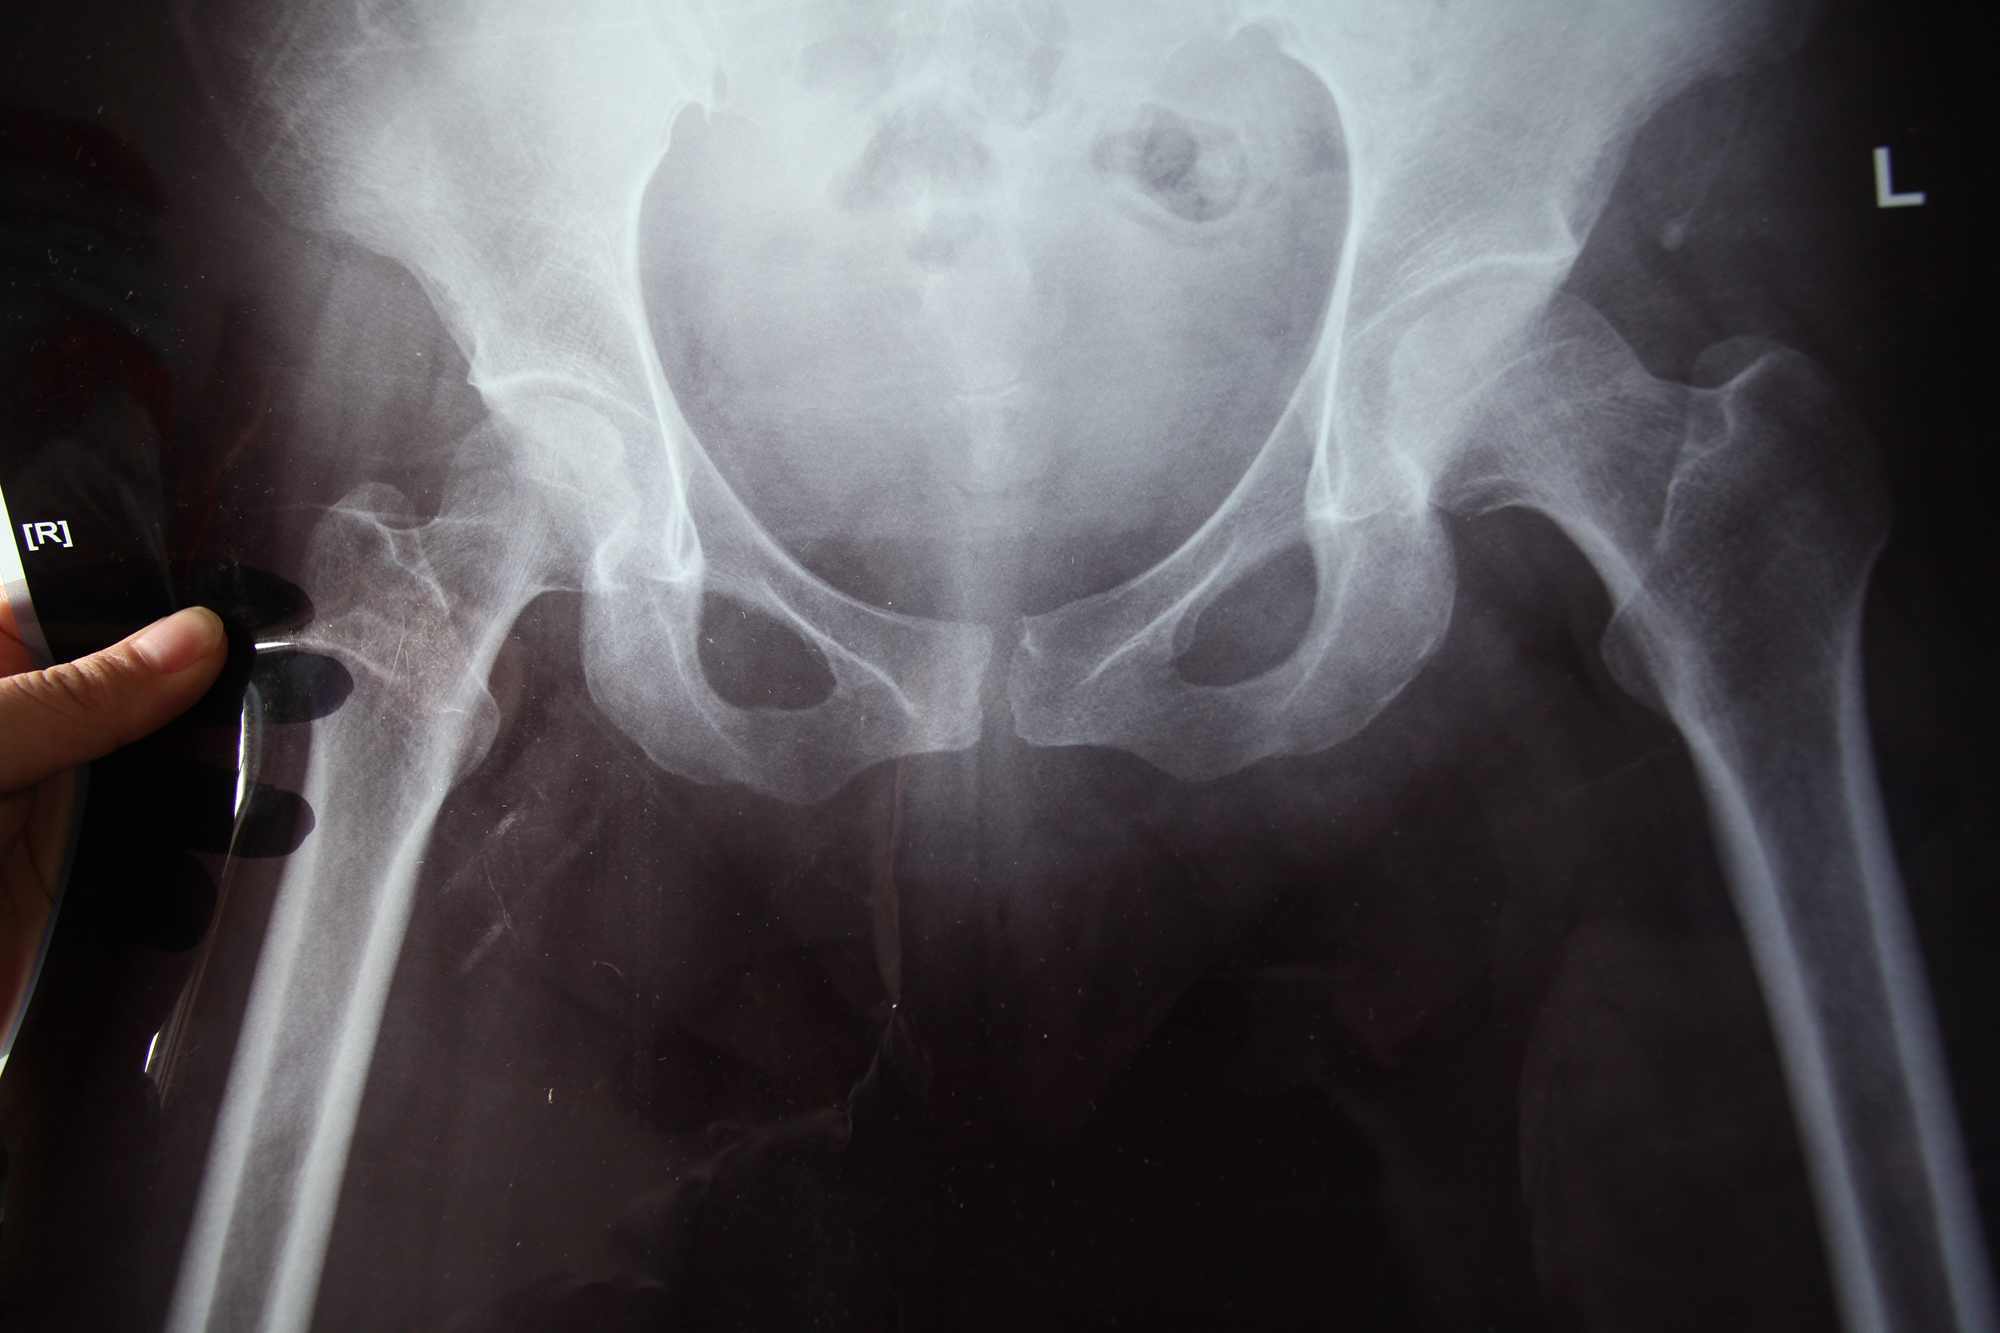

产后耻骨疼痛,不能侧卧,走路只能走几步,附X光片

2014年9月30日顺产,产后6小时按大夫要求下地在室内走了一圈,无明显不适,10月1日晚开始疼痛,无法入睡,自此卧床,大小便也不能去厕所,拍X光片,骨科说没什么大问题,耻骨分离在正常范围之内,建议静养,产科建议绑骨盆带,因为病房很热,断断续续绑了几次,没有什么明显改善,后医院产科又2次找骨科大夫查看,都说没什么大问题,对于骨盆带绑不绑也说法不一,最后组织骨科专家会诊,专家也说没什么大问题,建议卧床一个月,骨盆带可绑可不绑,总之最后结论仍是静养……无奈,10月9日在感觉稍有好转的情况下出院回家,绑了一次骨盆带,觉得反而更疼,这两天可能由于走、坐比较多,有反复现象,现在只能勉强去个卫生间。我的问题:1、这到底是不是耻骨联合分离?不是又是什么?2、对于这种病有没有有效的治疗方案?3、骨盆带到底绑不绑?